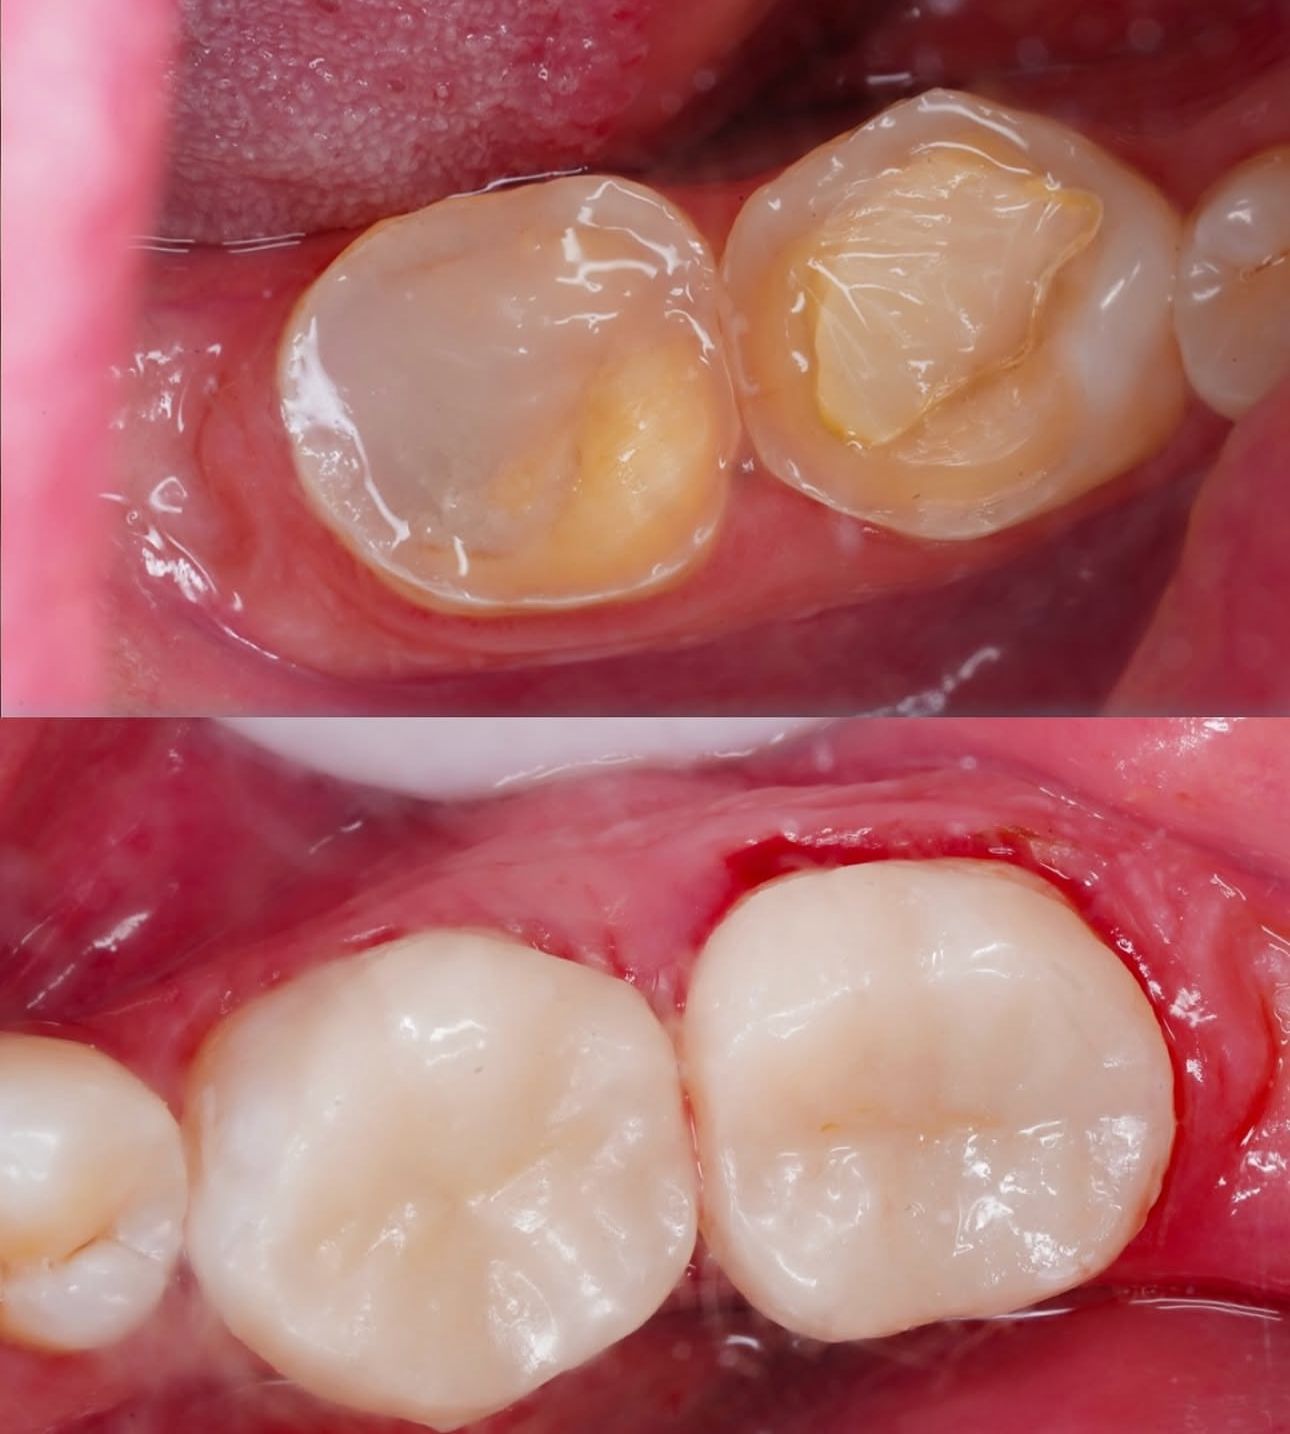

Dental Treatment Before and AfterClick To Enlarge White Teeth Lips Closeup Teeth Whitening Before After Teeth Whitening Transformation Before After Teeth Transformation Before After Man White Teeth Mustache Smile Teeth Whitening Transformation Before After Teeth Before After Transformation Teeth Before After Treatment Teeth Before After Composite Bonding Teeth Whitening Transformation Before After dental treatment dental treatment dental treatment dental treatment dental treatment dental treatment dental treatment dental treatment dental treatment dental treatment dental treatment dental treatment dental treatment dental treatment dental treatment dental treatment dental treatment dental treatment dental treatment